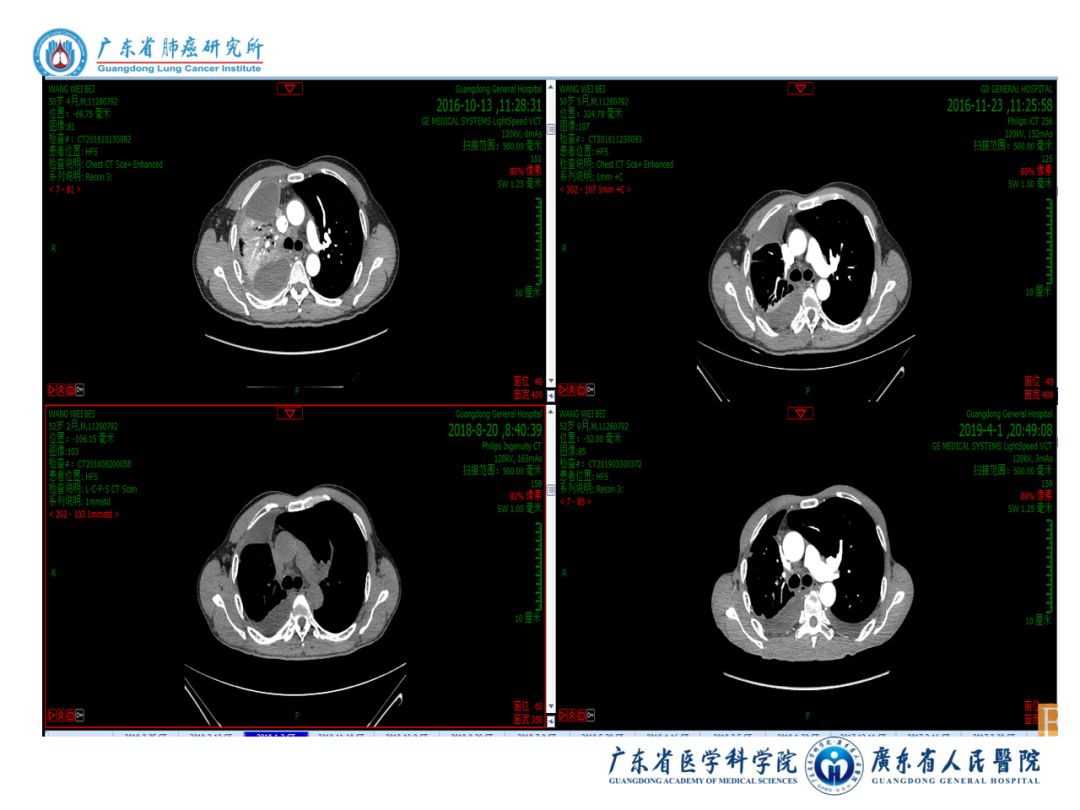

图表资料

病例小结

1)中年男性,晚期肺腺癌病程2年余,目前PS评分1分。

2)2016-09-09:EGFR、MET阳性

一线:A+T,PR  PFS30.0月

3)2019-04-09NGS:EGFR、TP53、TMB阳性